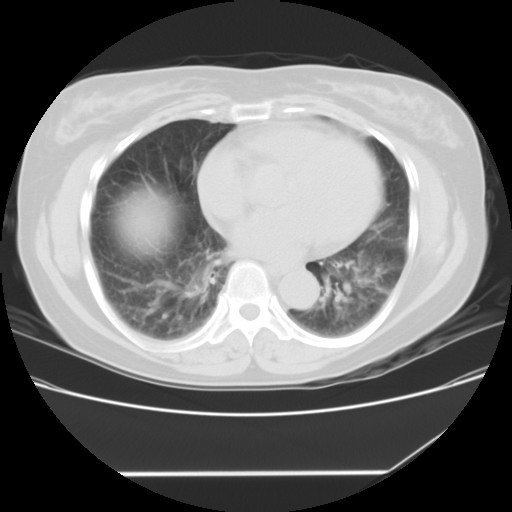

标题: CT24018:女性,62岁,咳嗽4年,无热,胸部CT扫 [打印本页]

女性,62岁,长期咳嗽,既往从事工作有粉尘接触,有高血压病史,110/150mmhg,近日咳嗽加重,脸面浮肿,请大家帮看下,

1、尘肺;2、慢性支气管炎合并肺部感染;3、心影增大(左房、左室大),考虑高血压性心脏病。

慢支并肺部炎症;右肺结核球?主肺动脉、右肺动脉影不宽,右心室不大,不支持肺心病;无心包积液。

右肺无结核球,是肝上缘

1)慢性支气管炎并肺部感染、肺气肿。2)肺间质纤维化。

间质性肺炎,左下肺机化性肺炎。